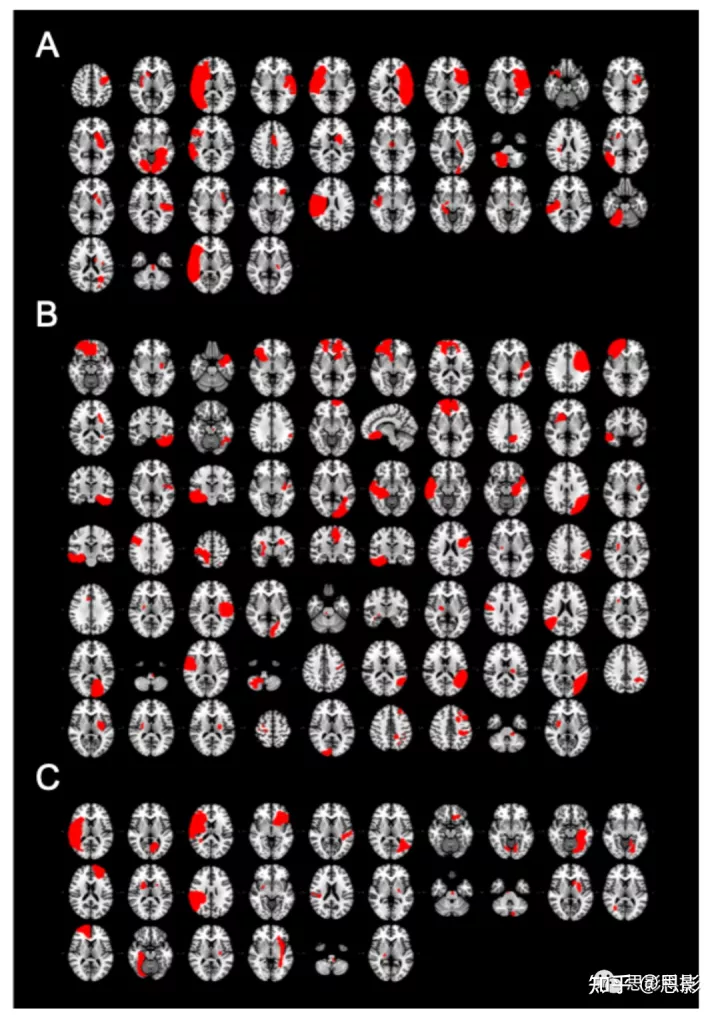

图 S1:吸烟者队列病变。

导致吸烟成瘾缓解的病变(A,n = 34)。未戒烟患者的病变(B,n = 69)。戒烟但未缓解的患者的病变(C,n = 26)。每个切片代表不同的患者。组间的病变大小没有差异(单因素方差分析,F = 1.78,p = 0.17)。

图 S2:病变位置和体素-病变症状映射(voxel-lesion symptom mapping, VLSM)结果。

在我们的两个队列(n = 129)中结合每天活跃吸烟者的病变位置,并叠加生成所有病变(A)或与特定临床结果相关的病变(B)的病变覆盖图。体素强度反映了与每个脑体素相交的病变数量。构建 VLSM z-map 以识别爱荷华数据集(C,左)、罗切斯特数据集(C,中)和两个数据集(C,右)的成瘾缓解最相关的体素。暖色表示成瘾缓解组中的体素更可能受损,而冷色表示非戒烟者中的体素更可能受损。使用爱荷华州(C,左)和罗切斯特(C,中间)队列构建的成瘾缓解 VLSM z-map 与预期相似。由于没有与成瘾缓解显著相关的体素,VLSM 地图显示为未阈值。